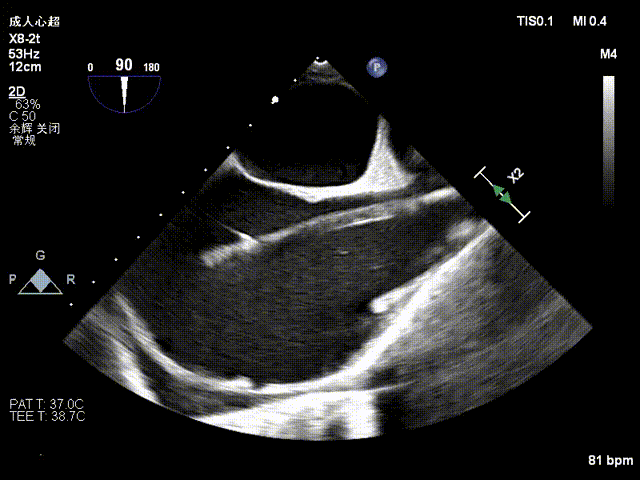

Echocardiographic findings indicated: Type IIIB quadrileaflet tricuspid malformation with extremely severe tricuspid regurgitation (5+, vena contracta: 16.1 mm on average). Regurgitant orifices were located at the anterior-septal, central, and posterior-septal regions, with a 11 mm central gap, leaflet tethering (tethering height: 10 mm), and tricuspid annular dilatation (mean annular diameter: 53 mm). The inferior vena cava diameter was approximately 25 mm, and RV FAC was 40%.

Baseline regurgitation after anesthesia